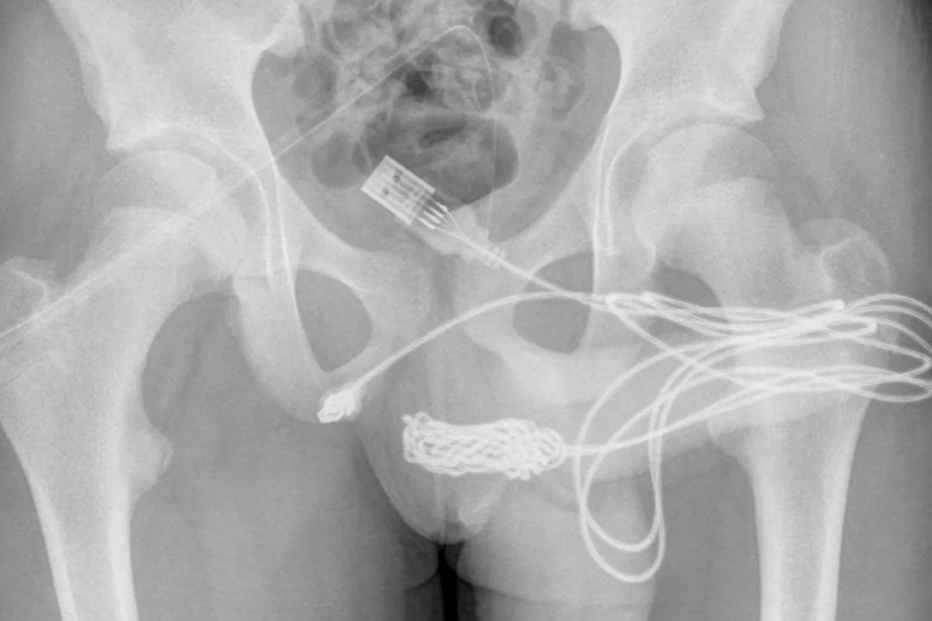

Um adolescente britânico acabou numa mesa de operações depois de inserir um cabo USB no pénis... porque queria medir o tamanho do órgão.

Após ser examinado, os médicos constataram que o jovem de 15 anos tinha um cabo dentro do órgão genital.

O adolescente, envergonhado, disse aos médicos que tinha inserido o cabo na uretra para medir o comprimento do pénis "por curiosidade sexual" e que tinha tentado retirá-lo, mas não conseguiu.